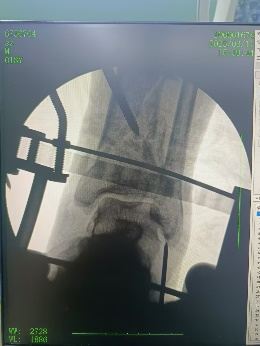

安裝外固定架

手術結束